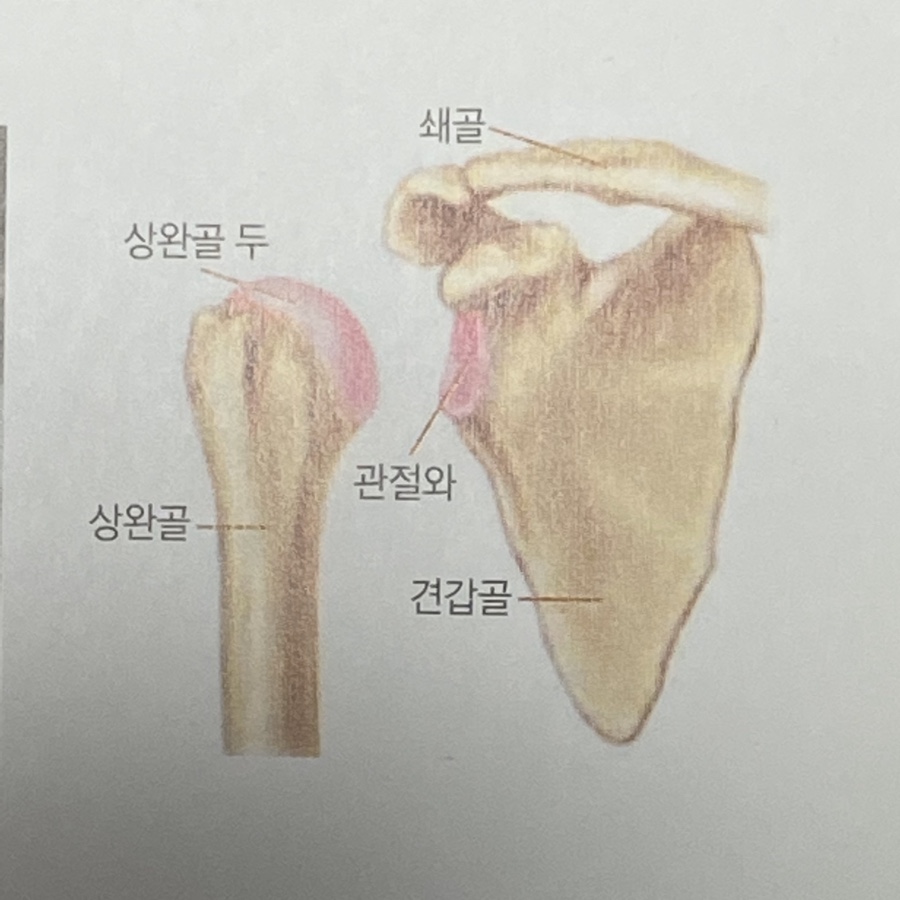

정상 어깨 관절은 어떻게 생겼나?

어깨 관절은 상완골의 골두와 견갑골의 관절와가 만나

움직임이 가능한 관절로, 관절을 이루는 면은

연골로 구성되어 있고 이 연골은

충격 흡수 그리고 통증없이 부드럽게 관절이 움직일 수

있도록 돕는 역할을 해요